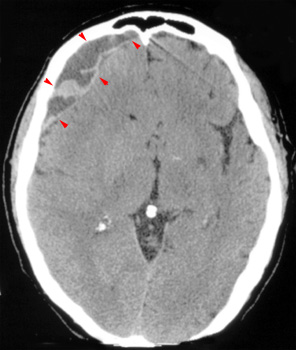

Head CT > Trauma > Chronic Subdural Hematoma

Chronic Subdural Hematoma

Chronic

SDH becomes low density as the hemorrhage is further reabsorbed. It is

usually uniformly low density but may be loculated. Rebleeding often occurs

and causes mixed density and fluid levels.